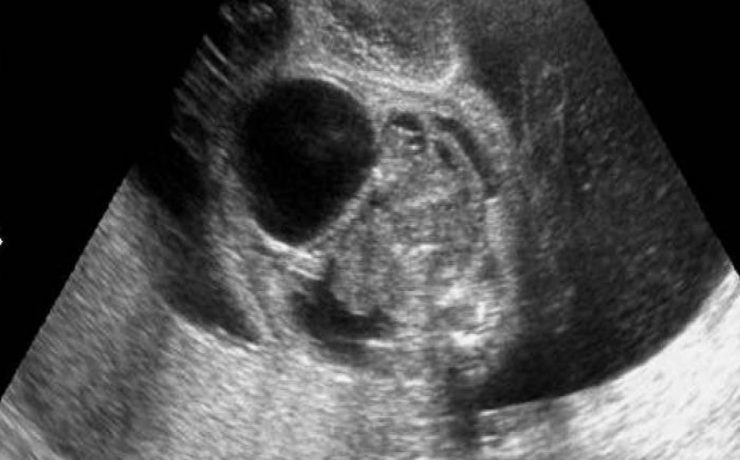

Hiperplasia prostática benigna

La hiperplasia prostática benigna (HPB) es muy prevalente en atención primaria; es el principal motivo de consulta por problemas urológicos en el hombre y es el primer diagnóstico que debemos pensar ante un paciente mayor de 50 años que consulta por síntomas obstructivos y/o irritativos. El diagnóstico de HPB es